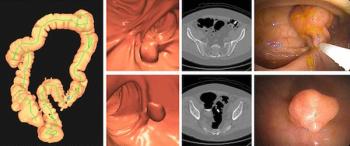

Computed tomography colonography (CTC) demonstrated a 91.6 percent positive predictive value (PPV) for polyps > 6 mm, according to new research involving over 9,000 patients who underwent CTC for primary asymptomatic colorectal cancer screening.

Researchers also noted a greater than 30 percent increase in treatment management changes resulting from the use of CT-based adjunctive AI to detect lung metastases in colorectal cancer patients.

Emerging research suggests the use of computed tomography colonography (CTC) in colorectal cancer screening may provide significantly higher preventive benefit at lower costs in comparison to multitarget stool DNA testing.